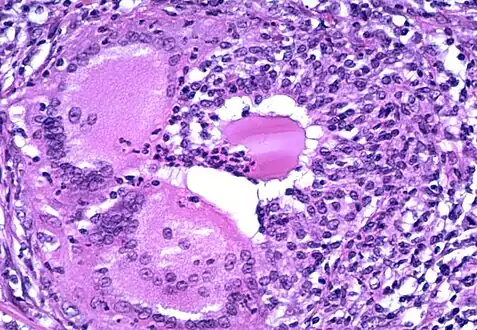

- a) Grade 1 thyroiditis characterized by presence of increased number of lymphocytes b) Grade 2 thyroiditis shows the presence of Hurthle cells, epithelioid cells, giant cells, and anisonucleosis c) Grade 2 thyroiditis shows the presence of Hurthle cells with lymphocytic infiltration d) Grade 3 thyroiditis characterized by presence of florid lymphocytic infiltration

- Microscopic image showing inflammation of the thyroid tissue